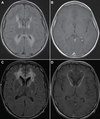

Dentatorubral-pallidoluysian atrophy is caused by a CAG trinucleotide repeat expansion of the polyglutamine region of the atrophin-1 gene on chromosome 12p. Because it is most associated with ataxia, choreoathetosis, and dementia, it is most similar to Huntington disease (HD). In young-onset cases, seizures and myoclonus are also common. Although MRI may show cerebellar atrophy, as here, it also shows brainstem atrophy, calcification of the basal ganglia, and leukodystrophic changes.